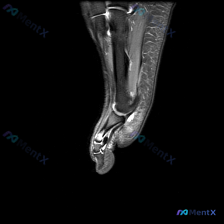

给大家分享一份最近遇到的踝关节MRI读片病例,初始问题指向软骨异常,整理一下完整的分析思路,一起讨论。 一、病例影像基本信息 这是一份踝关节矢状位T2加权MRI图像,图像质量好,信噪比高,解剖结构清晰,涵盖了胫骨远端、距骨、跟骨、足舟骨、骰骨及部分跖骨基底部,胫距关节、距下关节、窦跗管、跟腱等关键结...